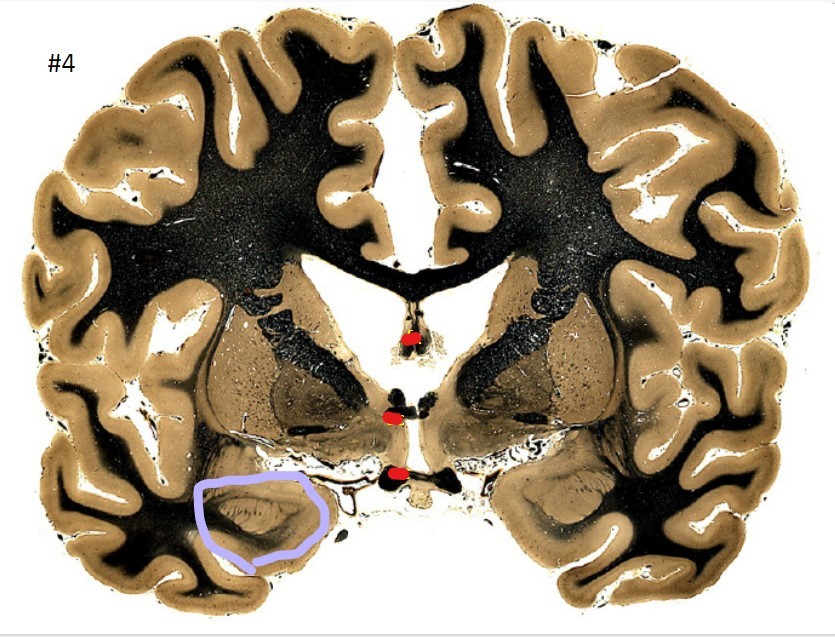

Q

what is the circled area (#4)?

A

the fornix

11

the anterior commissure

12

the optic chiasm

13

the putamen

14

the globus pallidus

15

the internal capsule

16

the caudate nucleus

17

the corpus striatum